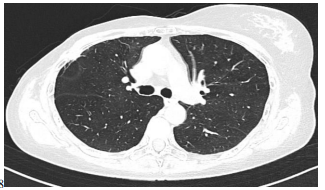

One month later patient underwent to thoracic Hight Resolution Computed Tomography (HRCT) scan that showed a single node localized in right intercostal space (Figure 1).

Figure 1: Thoracic Hight Resolution Computed Tomography image.

A single node localized in right intercostal space is detected (December, 2021).